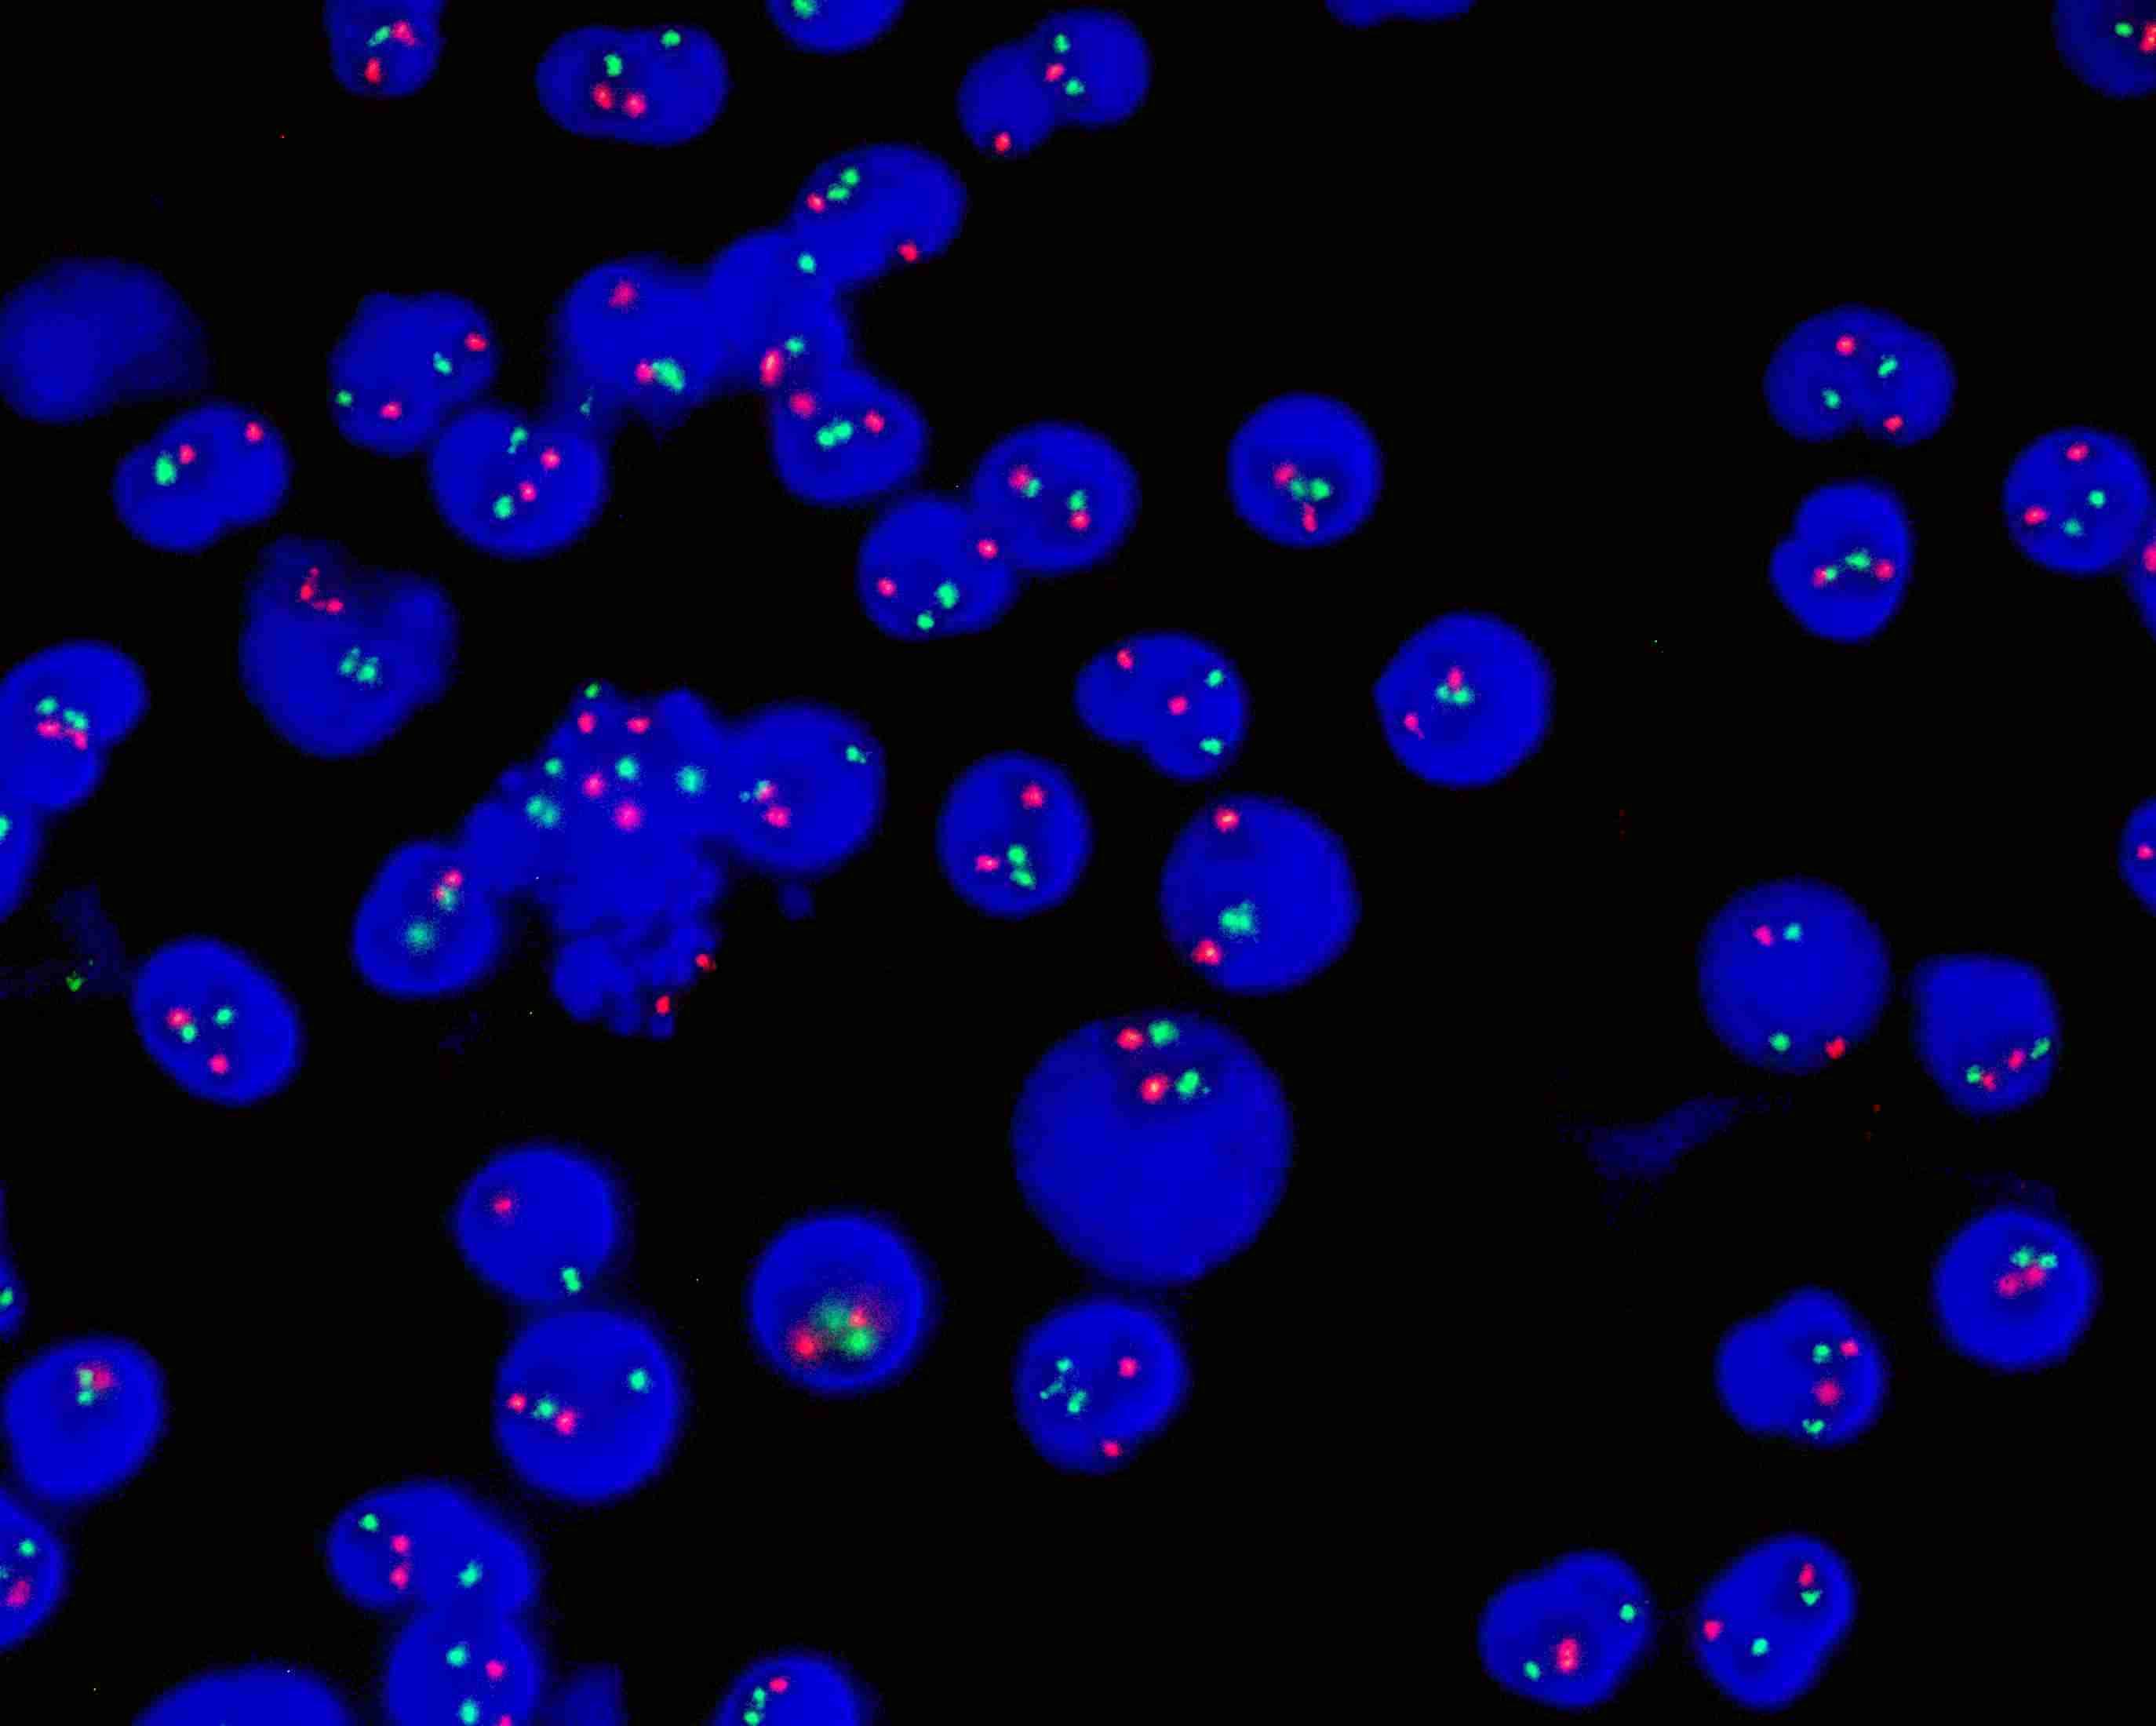

ETV6(TEL)/RUNX1(AML1) dual color probe(TEL orange/AML1 green)

ETV6(TEL) gene labeled as orange, with a total length of 600 kb; AML1(RUNX1) labeled as green, with a total length of 1100 kb.